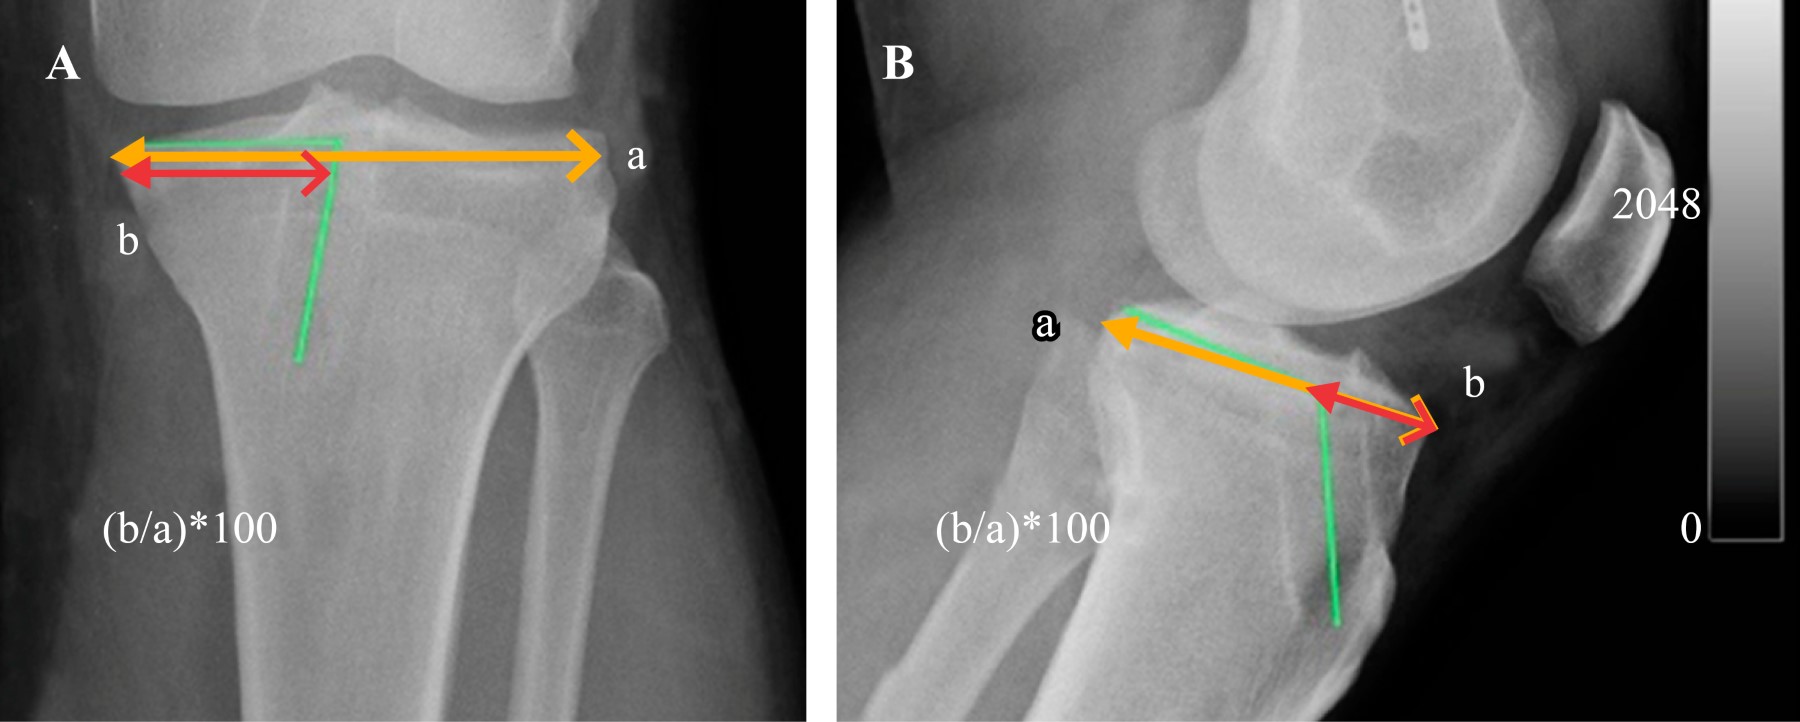

Para evaluar la ubicación del túnel tibial6 se midió la ubicación en porcentaje de la localización con respecto al platillo tibial en el frente, se midió el ancho del platillo tibial y la distancia entre el extremo medial del platillo y el centro del túnel tibial expresado en forma porcentual. En el perfil se midió la distancia anteroposterior del platillo tibial interno y la distancia de la cara anterior de la tibia al centro del túnel tibial expresado en forma porcentual. El ángulo del túnel tibial en el frente es evaluado por una línea que pasa por el platillo tibial interno y su intersección con una línea que pasa por el centro del túnel tibial. El ángulo de inclinación del túnel tibial en el perfil es medido por una línea que pasa por el platillo tibial interno de anteroposterior y otra línea que pasa por el centro del túnel tibial que lo intercepta (Figura 2).

En tibia, la distancia porcentual en proyección anteroposterior fue de 44% y en la lateral de 28%; el ángulo del túnel tibial en proyección anteroposterior fue de 73° y en la proyección lateral fue de 114°.